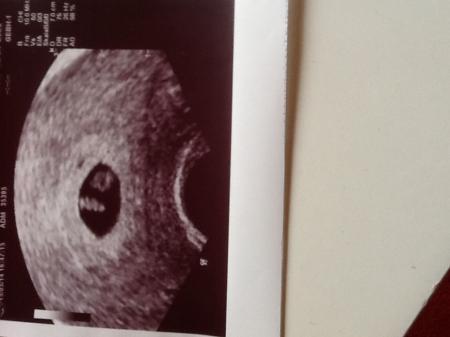

Also ich war das erste mal in der 6 ssw. Weil man nur eine Fruchthöhle sehen konnte sollte ich eine Woche später wieder kommen das war letzten Do....und da sah man schon den kleinen Knirps sogar das kleine Herz hat man schlagen gesehen und ein Bild hab ich auch mitbekommen. Nächste Woche Di soll ich wieder hin für den Mutterpass*freuuuuu*. Alsoooo sei schonmal gespannt das wird ganz aufregend in den nächsten Wochen ;-) Liebste Grüße

Aus grade aktuellen Erfahrungen hätte ich lieber gewartet ich war das erste mal 3 Woche und muss seid dem wöchentlich hin... Man sieht nur noch nicht so viel ... Bis man das Herz endlich bubbern sieht wird man wahnsinnig ... Hänge dir mal nen Bild dran wo man was sieht das war Donnerstag bei 5+3 Morgen muss ich wieder hoffe dann bubbert es